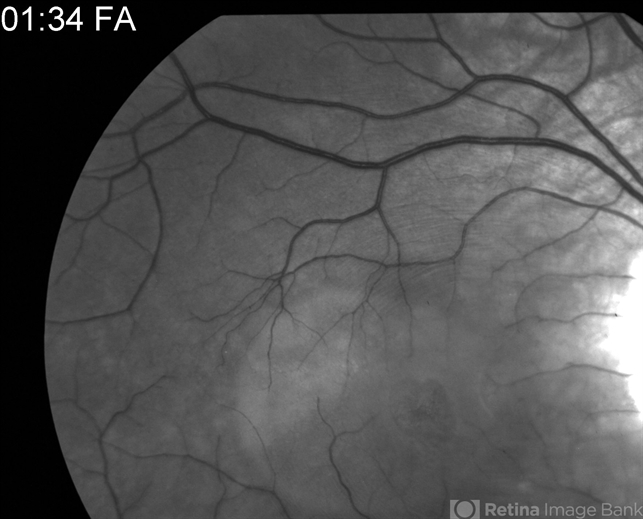

- Optic Nerve Pit Related Serous Detachment Treated by Vitrectomy with Laser and Gas

- congenital optic nerve pit, serous retinal detachment, pre-op, vitrectomy, vitreomacular surgery, red-free

- Pre-op red-free photo showing optic nerve pit and prior laser treatment at temporal aspect of optic nerve. Note the subtle outline of the serous retinal detachment.